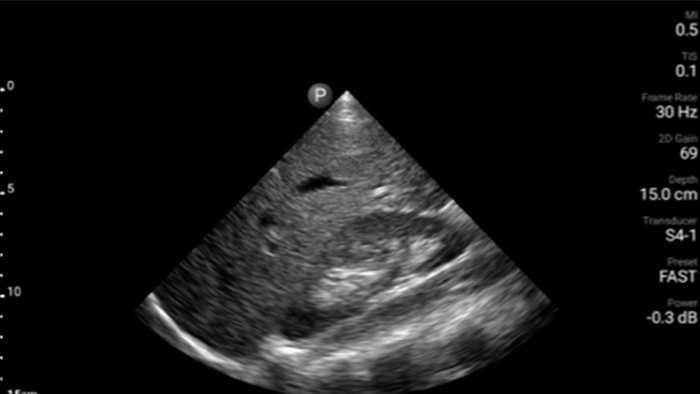

Verminder complicaties tijdens naaldgeleide procedures

De Lumify draagbare echografieoplossing voor loco regionale anesthesiologie helpt u bij het visualiseren van de omliggende zenuwen, vaten, omliggende weefsels en naald-in situ tijdens de procedure.